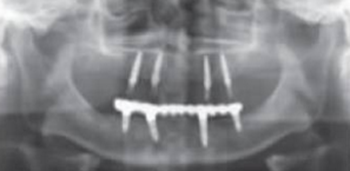

術(shù)后曲面斷層全景片(圖19)可見種植體在上頜位置較為理想,同時(shí)可見臨時(shí)義齒種植體開孔位置在13、23舌側(cè)、16、26牙合面近中,上下頜咬合關(guān)系理想。患者對種植臨時(shí)修復(fù)義齒滿意。

圖19 即刻修復(fù)后全景片